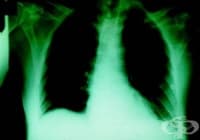

Саркоидозата (болест на Besnier-Boeck-Schaumann) е хронично мултисистемно грануломатозно заболяване,...

Въведение и исторически преглед Саркоидозата (sarco плът, месо; eidos подобно; osis състояние) е мул...